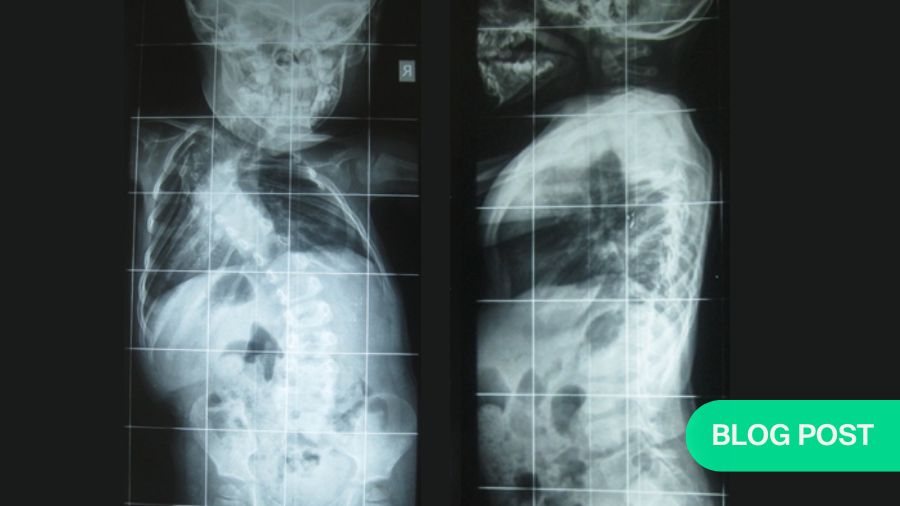

APC is a hybrid of guided growth and apex control through non fusion and reversed modulation-based philosophies for management of growing-spine deformity. It replaces the apical fusion of a traditional SHILLA with procedures (compression/distraction + medial translation + derotation) against primary drivers of curve progression, as shown in Figure 1, Figure 2.